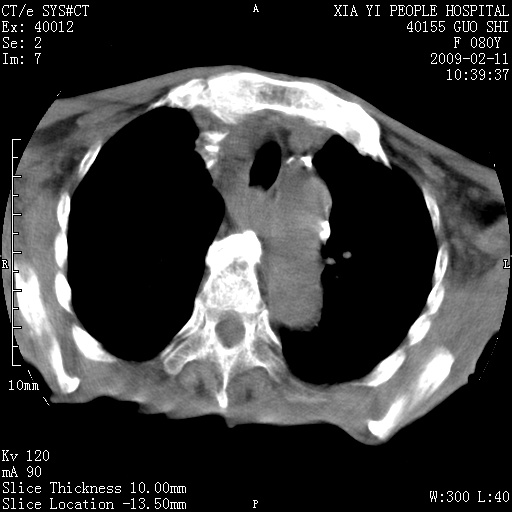

以下是引用随光逐影在2009-2-16 16:34:00的发言:[br]1)考虑右前纵隔皮样囊肿。2)双侧少量胸腔积液。

以下是引用zjzjr在2009-2-16 17:30:00的发言:[br]支持囊性畸胎瘤 双侧少量胸腔积液。